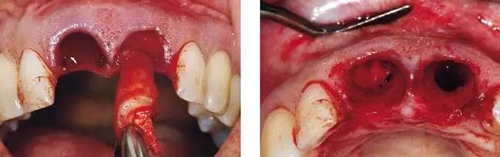

圖4、觸診檢查感知頰側(cè)有骨缺損,且瘺管與牙槽窩內(nèi)肉芽組織相連。

圖5、左側(cè)用探針檢查可感知牙槽窩根方頰側(cè)軟硬組織的缺損??梢?jiàn)牙間乳頭很薄。

圖6、前庭溝半圓形切口,翻瓣后暴露左側(cè)和右側(cè)的骨缺損。

圖7、去除了肉芽組織和根尖感染組織,仔細(xì)沖洗后,可見(jiàn)雙側(cè)拔牙窩唇側(cè)骨壁有大面積缺損。